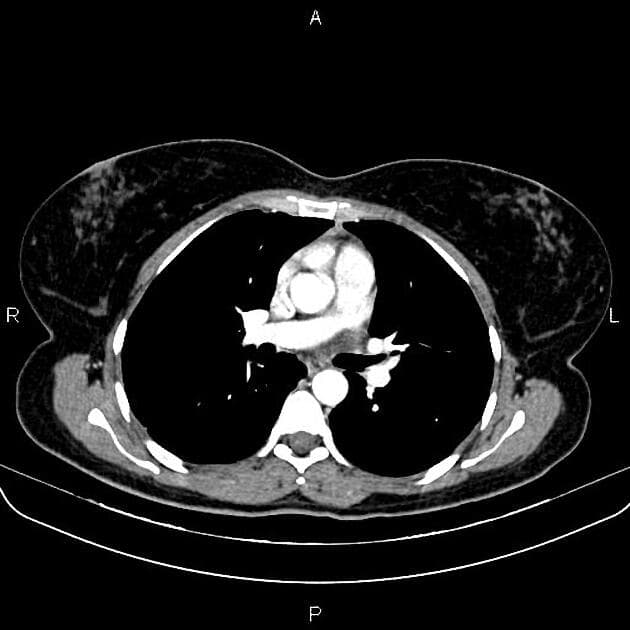

Nhiều tổn thương nội sọ bắt thuốc (enhancing intracerebral lesions), chủ yếu ở vùng hố sau.

Các tổn thương có dạng đặc, thay vì dạng nang với nốt đặc thành nang (cystic with a solid mural nodule).

Khối u thần kinh đặc trưng là u mạch máu nhân dạng tế bào (hemangioblastoma), có thể xuất hiện ở não hoặc tủy sống.

- "U mạch máu trong VHL thường đa ổ và có thể xảy ra ở tiểu não, thân não và tủy sống."